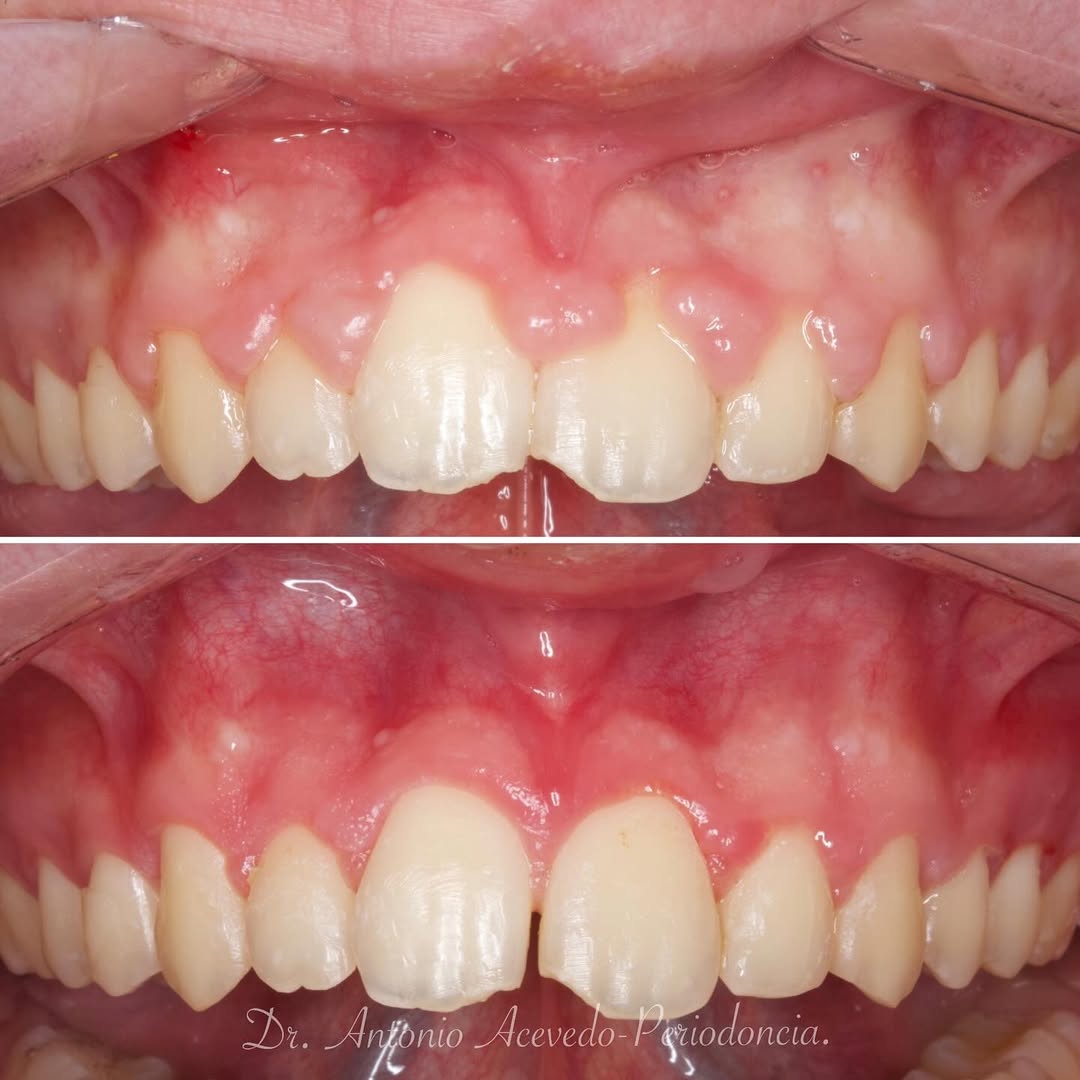

Una estancia clínica pensada para quienes quieran iniciarse o dar un paso más en el campo de la cirugía mucogingival. Durante esta experiencia tendrás la oportunidad de aprender en directo cómo

...El Dr. Alejandro Dulanto te mostrará su práctica diaria enfocada exclusivamente a Cirugía y Periodoncia. Asistirás a todas las citas que el mentor tenga agendadas y tendrás la oportunidad de ...

Una estancia clínica pensada para quienes quieran iniciarse o dar un paso más en el campo de la cirugía mucogingival. Durante esta experiencia tendrás la oportunidad de aprender en directo cómo se planifica y se lleva a cabo una cirugía mucogingival mediante técnica de Túnel.

La sesión